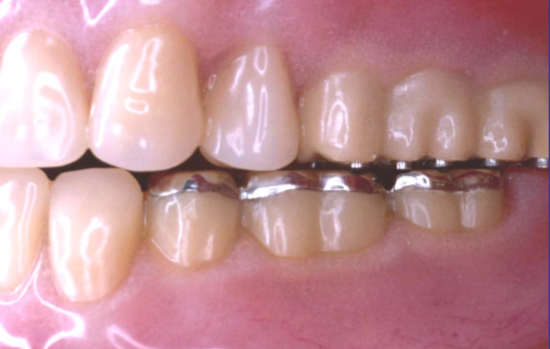

What are some advanced treatment options for edentulous patients?

What are some advantages of Overdentures?